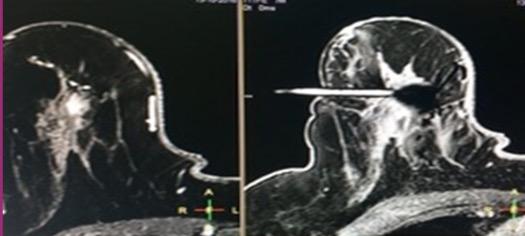

Figura 6: a) lesão-alvo; b) Visiloc introduzido para validação da sua relação com a lesão.

plástico estéril, trocarte, bloco e visiloc e um clip de titânio. Coloca-se o bloco na posição correta na grelha (Fig.5) A cânula é colocada no bloco (este permite até 13 diferentes posições de entrada). A seguir, o trocarte é inserido na cânula até atingir a profundidade calculada. Retirase o trocarte e coloca-se o visiloc, visível na RM. (Fig.6) Para validação o do processo e durante a sua execução é realizado um Axial T1 fatsat, para documentar a localização do Visiloc. (Fig.6) Este aparece como uma